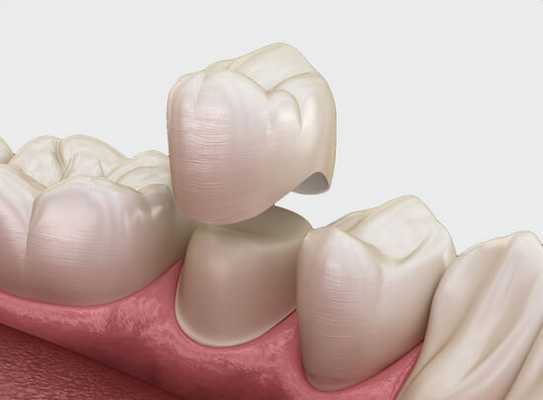

Протезирование коронками

Показано при значительных дефектах почерневшей зубной единицы, которые нельзя устранить остальными способами. Коронки из циркония и керамики E-max в точности повторяют оттенок зубного ряда пациента. Отличить их от настоящих сможет только врач.

Если потемневший зуб сильно разрушен или десна вокруг сильно воспалена, рекомендуют его удаление и установку дентального имплантата.